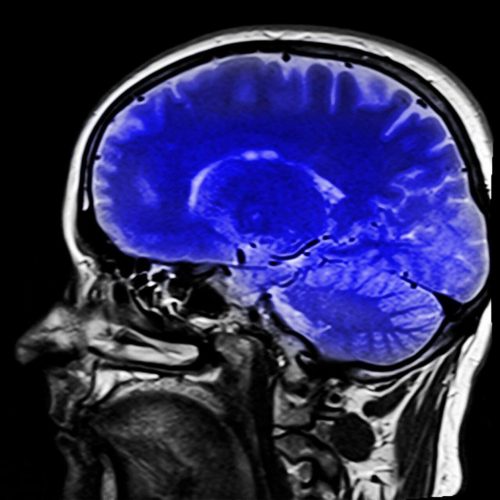

Der er neurologiske tests, der hjælper læger med at diagnosticere dette syndrom. MR-scanninger kan vise, hvilken slags slagtilfælde der er sket, og dette vil hjælpe dem med at finde ud af, hvad det er.